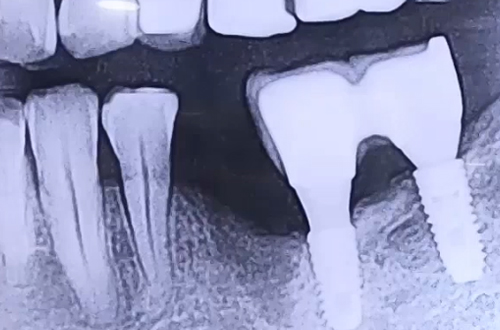

임플란트는 몸통 부분과 머리 부분 (임플란트 보철 부분), 중간 보철로 이루어져 있습니다.

임플란트 수술 시 우선 몸통 부분을 잇몸에 식립한 뒤

단단히 굳고 나면 그 위에 머리 부분인 임플란트 보철을 연결하는데요.

이 연결을 해 주는 것이 중간보철 구조물이라고 할 수 있겠습니다.

임플란트 몸통 안쪽에는 나사 홈이 있어서, 중간 부품은 바로 거기에 들어가

나사로 조여주며 고정되고 결합이 되며, 이 나사는 머리 부분의 보철 안 구멍으로 볼수 있죠.

이 구멍은 이후 치아 색과 같은 재료로 덮어 채워주게 되는데요.